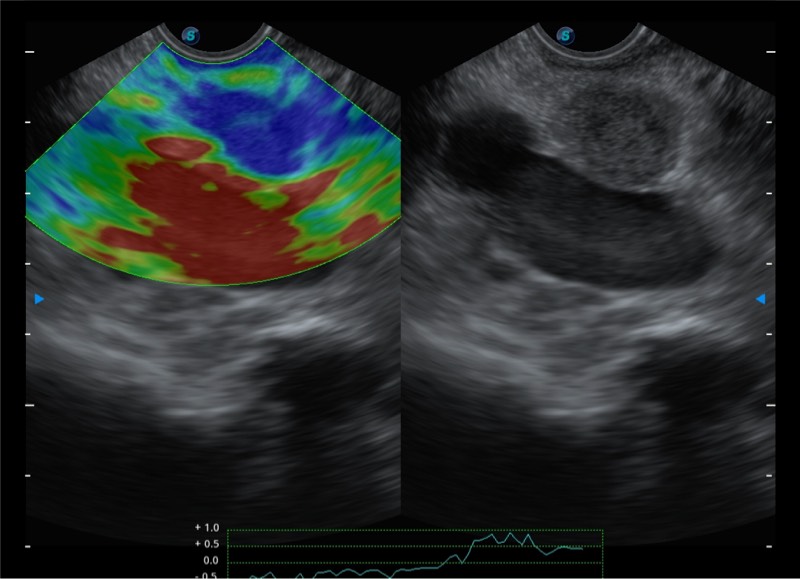

基于二十年的超声技术积累,诸侯快讯官网提供了最新一代的独立超声主机,在提供高质量图像的同时满足多学科使用。具备常见多普勒技术并提供弹性成像、声学造影等高端影像技术。新一代传感器具有更强的抗干扰能力并减少图像伪影。